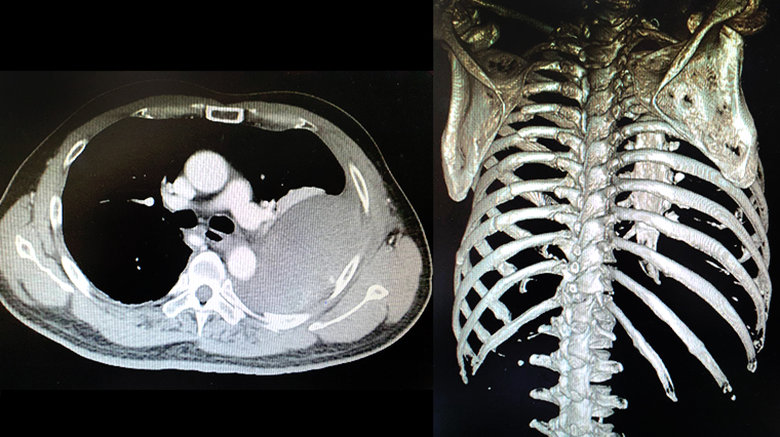

1名56歲湯姓男子近日發生車禍,被送往醫院治療,在胸部X光檢查時發現左側1根肋骨骨折,因此安排住院接受疼痛控制,2天後要準備出院時,卻還是覺得不太舒服,再次以X光追蹤檢查,沒想到受傷的左側瀰漫霧白,情況惡化相當嚴重,立即轉院至澄清醫院中港分院接受進一步的治療。

收治這名湯姓男子的台中澄清醫院中港分院胸腔外科主任暨外科部部長賴重佑指出,急診初步了解患者的情況時,不敢相信1根肋骨骨折會出現如此大的變化,且湯姓男子並無服用任何抗凝血藥物的病史,再回溯先前醫院準備的所有檢查影像,確定湯姓男子受傷當下的胸部X光,並無出現嚴重的肋骨和肺臟損傷,經詳細解釋後,患者的妻子願意接受這是非常罕見的併發症,而非誤診,避免可能發生的醫療糾紛。

湯姓男子被轉院後,重新接受了相關檢驗,並進一步使用顯影劑做電腦斷層掃描,檢查發現他的血小板只剩7萬,一般成人的血小板正常值應該要有15至40萬,且影像上看到多根肋骨節狀骨折的連枷胸,併發非常罕見的巨大肋膜下血腫,檢查當下還在急性出血中,因此徵求病人及家屬同意後,立即進行了緊急手術治療血胸,並以肋骨固定手術降低骨折疼痛、肺臟合併症,縮短住院時間,並挽救了湯姓男子一命,術後照護一切順利,也未發生感染問題。